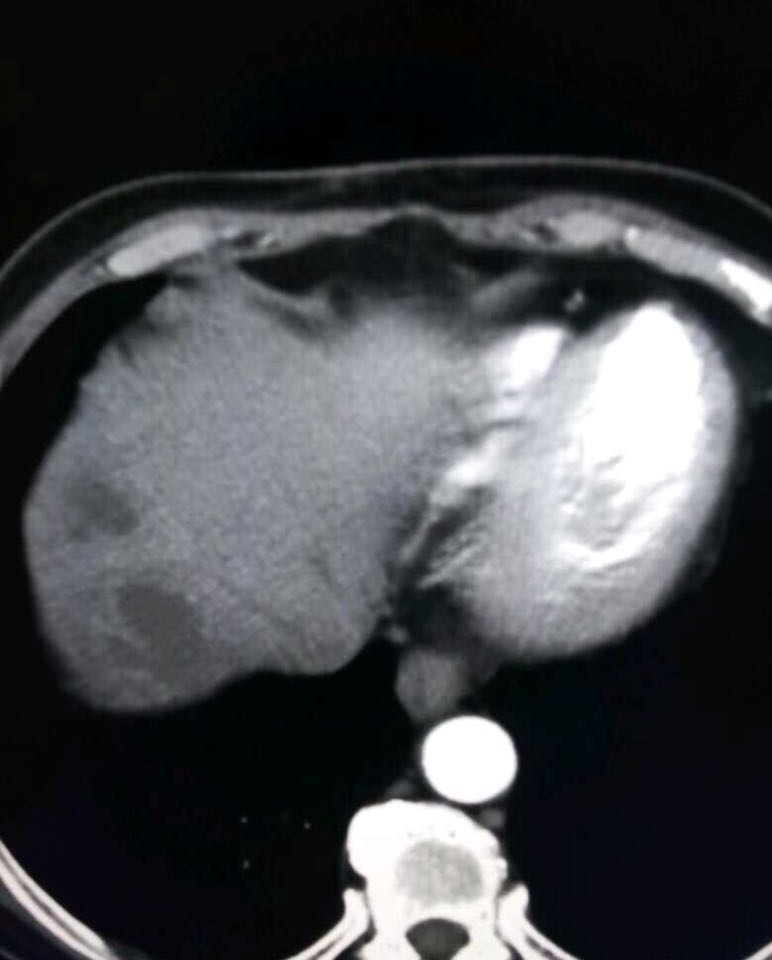

患者以高热,寒战入院,无其他明显症状,行肺CT扫描提示肝脏低密度灶随行腹部增强,发现肝脓肿脓腔形成伴多发间隔,多发子灶,怎么处理?

病例点评: 阿米巴肝脓肿系阿米巴原虫穿过肠壁,经门静脉至肝,在肝内门静脉末梢支拴塞、缺血,同时产生溶组织酶导致细胞坏死而形成的肝脓肿。脓腔较大,多单发,右叶较多。本病多发生在热带或亚热带,在我国不如化脓性肝脓肿多见。CT扫描表现为类圆形低密度区。脓腔内密度不均匀,与坏死程度有关。边缘比较清楚,周围的肉芽组织有增强效应。增强后可为等密度以致病灶缩小。